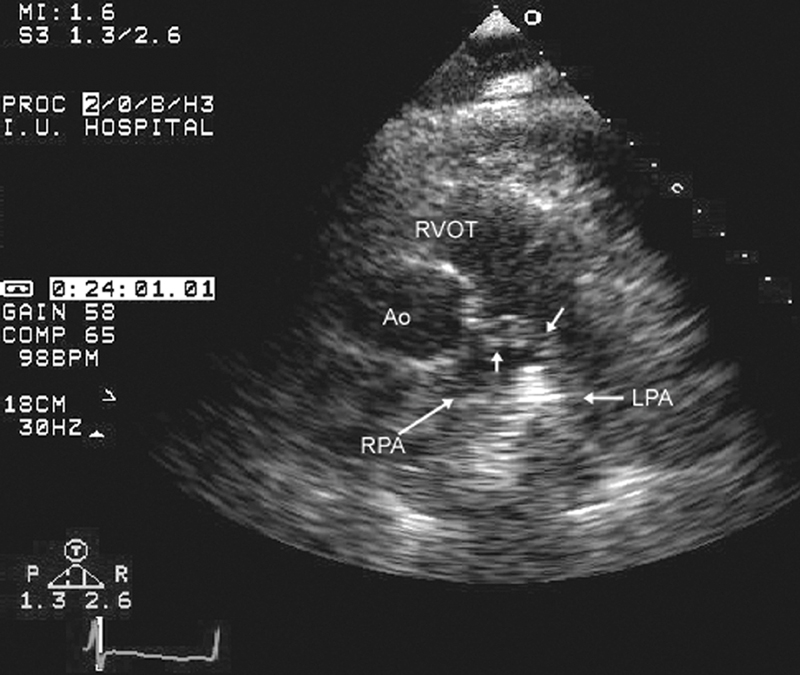

فحوصات تشخيصية لبعض امراض القلب والشرايين التاجية